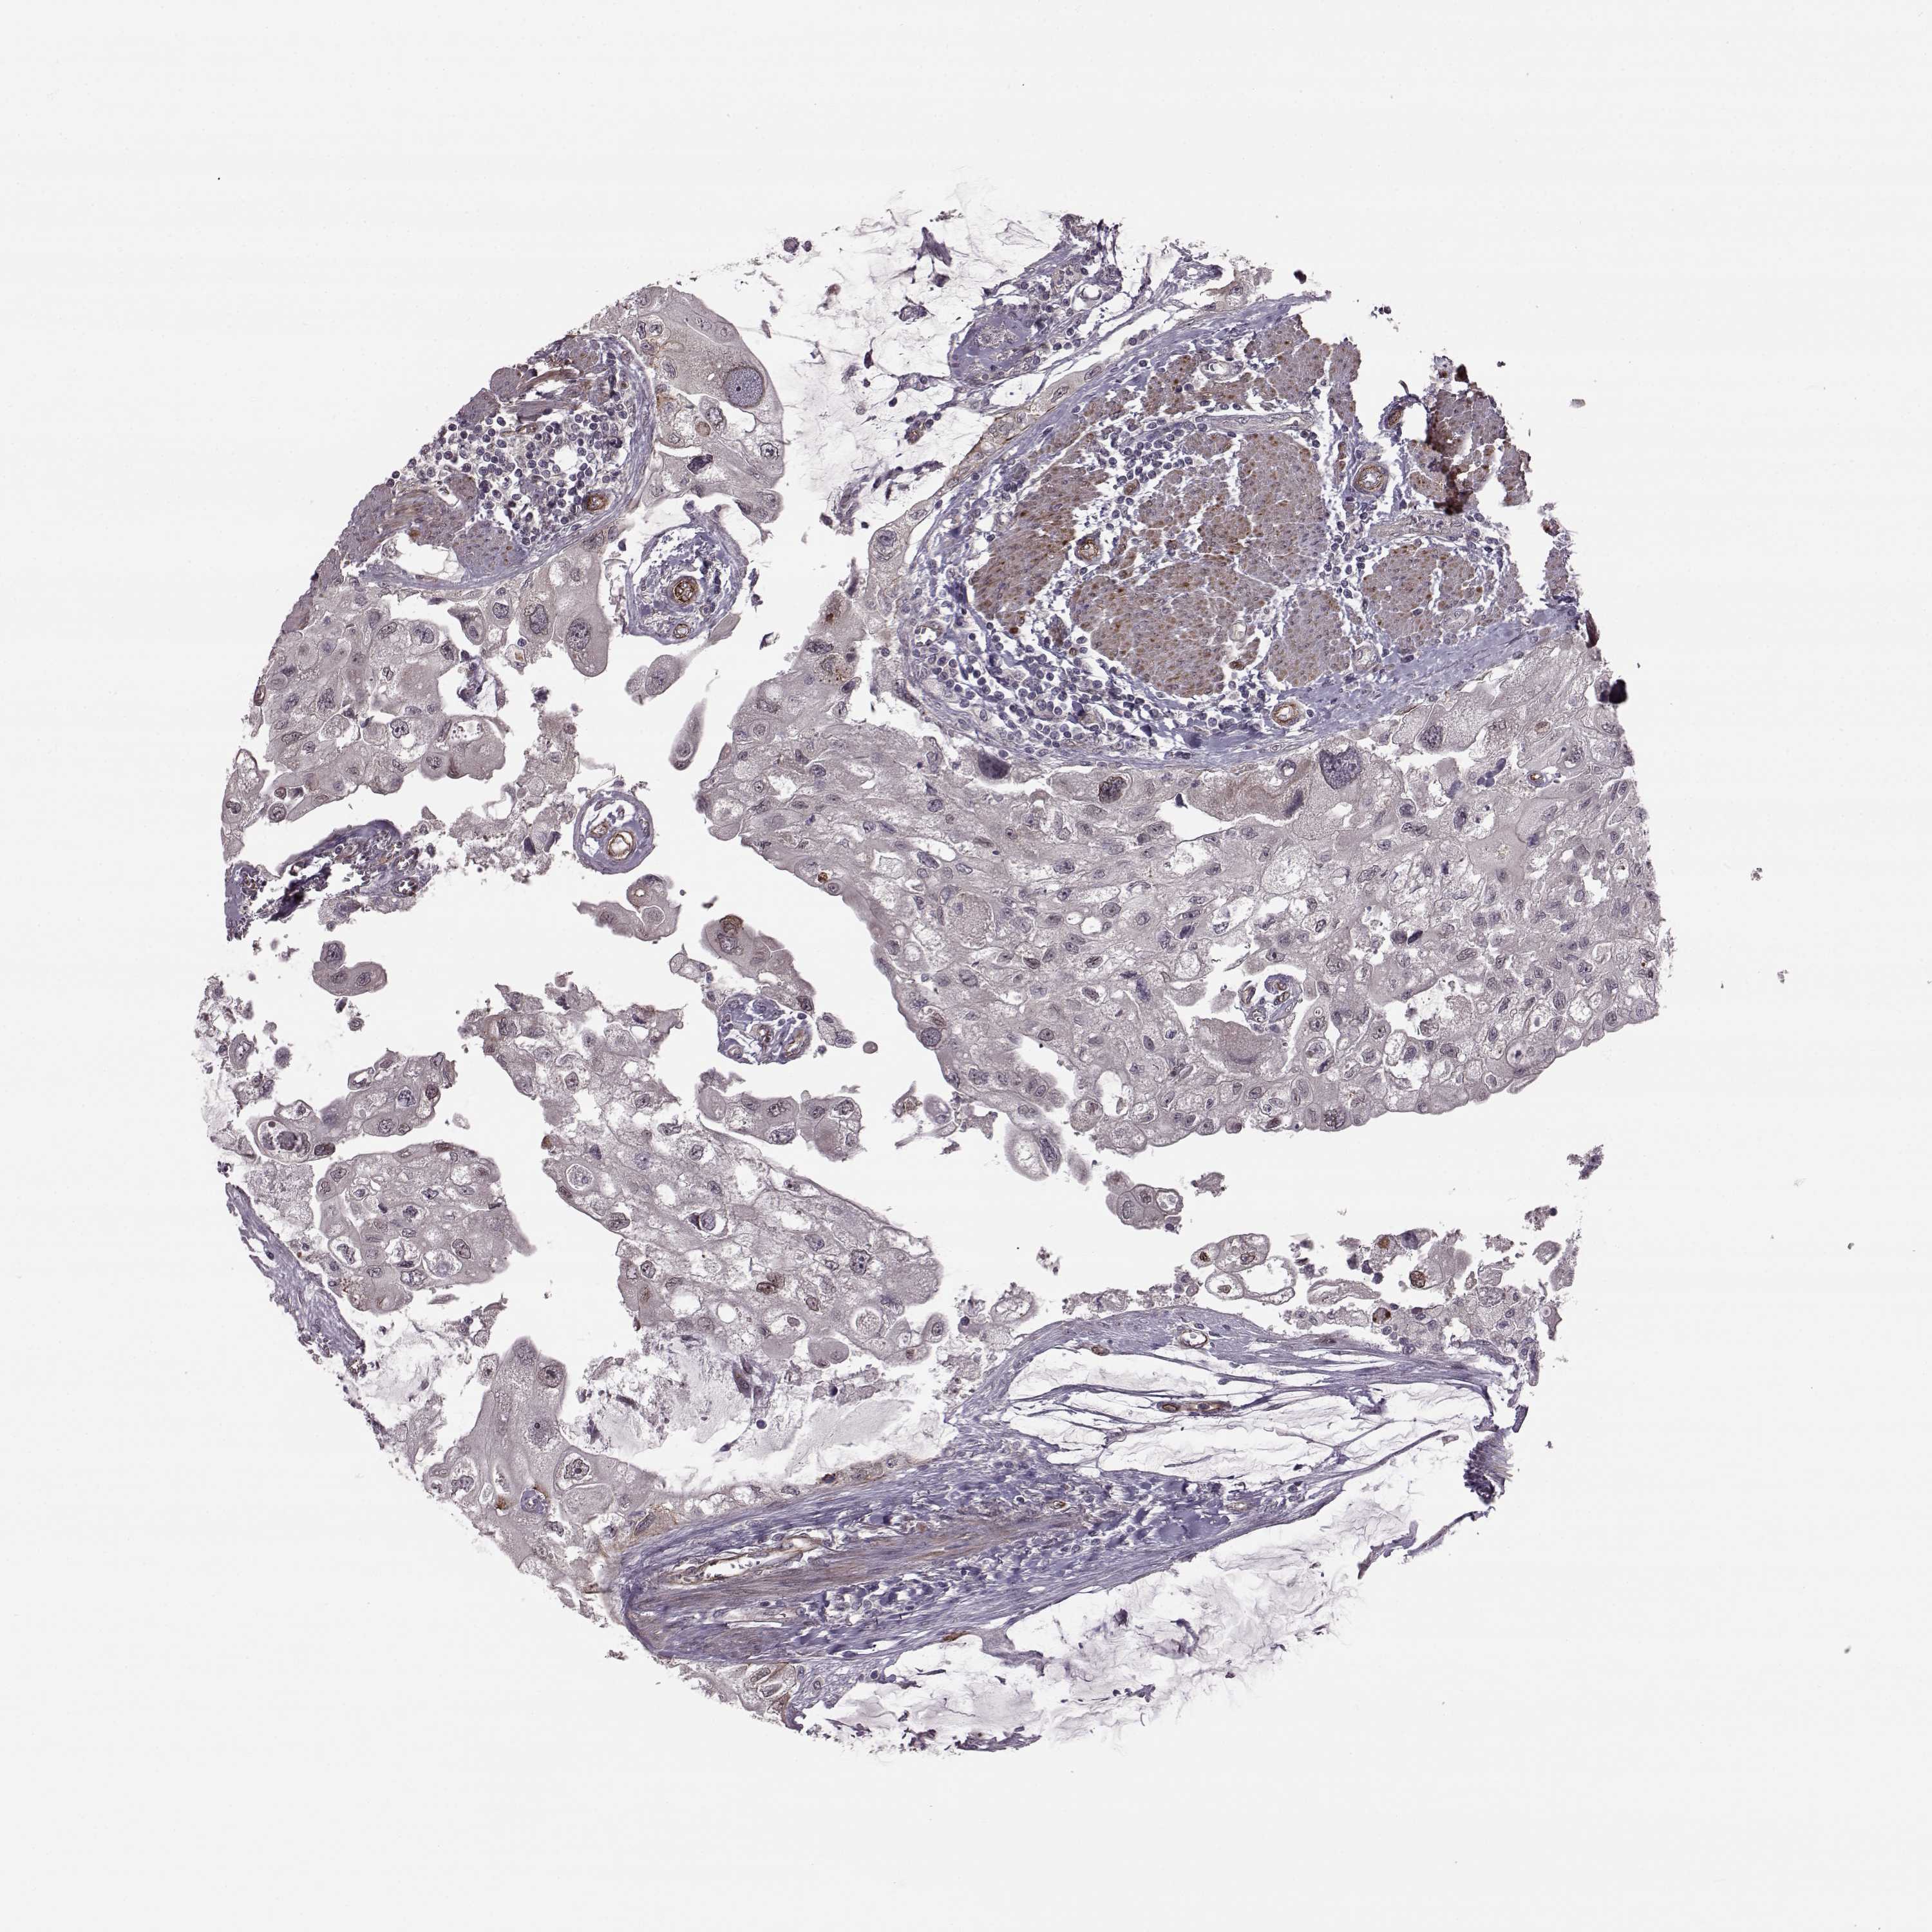

UROTHELIAL CANCER - Protein expressioni

A mouse-over function shows sample information and annotation data. Click on an image to view it in a full screen mode. Samples can be filtered based on level of antibody staining by selecting one or several of the following categories: high, medium, low and not detected. The assay and annotation is described here.

Note that samples used for immunohistochemistry by the Human Protein Atlas do not correspond to samples in the TCGA dataset.

Antibody stainingi

Antibody staining in the annotated cell types in the current human tissue is reported as not detected, low, medium, or high, based on conventional immunohistochemistry profiling in selected tissues. This score is based on the combination of the staining intensity and fraction of stained cells.

Each image is clickable and will lead to virtual microscopy that enables deeper exploration of all samples and also displays staining intensity scores, fraction scores and subcellular localization as well as patient and tissue information for each sample.

Antibody HPA034631

Urothelial carcinoma, High grade

Urothelial carcinoma, Low grade

Urothelial carcinoma, NOS